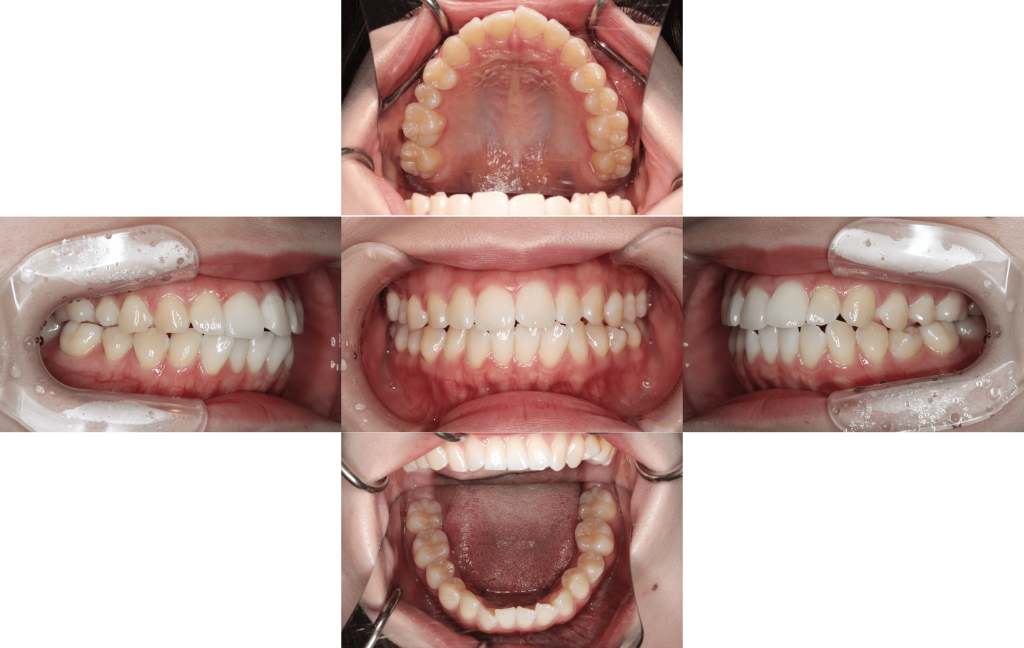

装置装着